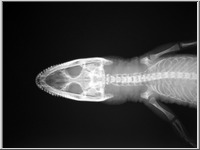

A képekre kattintva a röntgenfelvételek üveglemezeinek reprodukcióit, a kis képek jobb felső sarka melletti ikonokra klikkelve pedig az üveglemezeket védő, Gothard által feliratozott, a felvételek adatait tartalmazó borítékok reprodukcióit láthatjuk.

Az 1. sorszámú lemez elveszett, csak papírmásolat maradt fenn róla. A 25. és 26. sorszámú borítékok 2-2 felvételt tartalmaznak (itt a-val és b-vel jelölve), míg a 32. sorszámú lemez eltört, két darabban van.